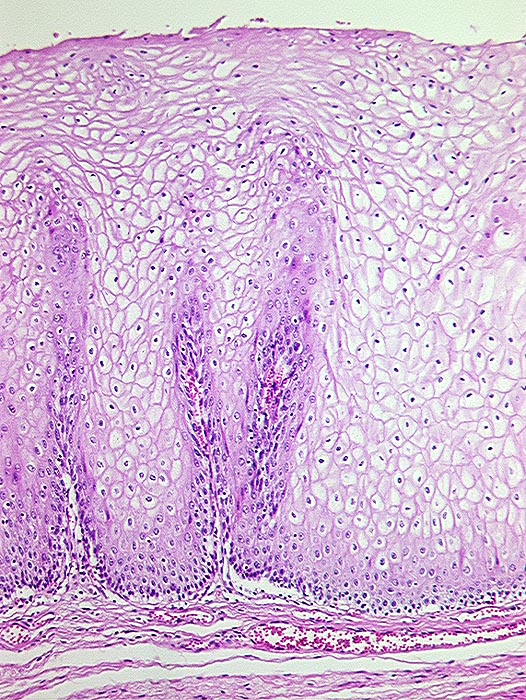

Morphologische Merkmale:

• Polypoides exophytisches Karzinom.

• Tumordurchbruch durch die Lamina muscularis mucosae in die Submukosa.

• Der Tumor bildet anastomosierende solide Zellstränge, die fokal im Zentrum verhornen.

• Tumorzellen mit reichlich glasigem eosinophilem Zytoplasma und scharfen Zellgrenzen mit stachelförmigen Interzellularbrücken. Stark vergrösserte, pleomorphe, hyperchromatische Zellkerne mit prominenten Nukleolen.

• Zwischen den Tumorzellsträngen desmoplastisches Stroma mit dichtem gemischtem Entzündungsinfiltrat.

• Präneoplastisch veränderte Mukosa im Randbereich des Karzinoms mit ausgeprägten Zellatypien in der gesamten Epithelbreite und zahlreichen Mitosen (Carcinoma in situ).